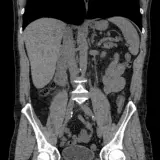

Over 2,100 interactive radiology cases, curated by radiologists for your level of training. Scroll, window, and view cases full screen โ€” just like on PACS. Click linked findings in each writeup to jump straight to them on the image. Cases include sample reports, a focused discussion section, original illustrations, and videos.

Casi completamente interattivi con gli strumenti che ti aspetti su un PACS: scroll, windowing, zoom, pan, misurazioni, ROI e modalitร  a schermo intero.

Annotazioni dettagliate evidenziano i reperti chiave direttamente sui casi. Clicca sui reperti collegati nella descrizione del caso per saltare alla loro esatta posizione sullo scan.